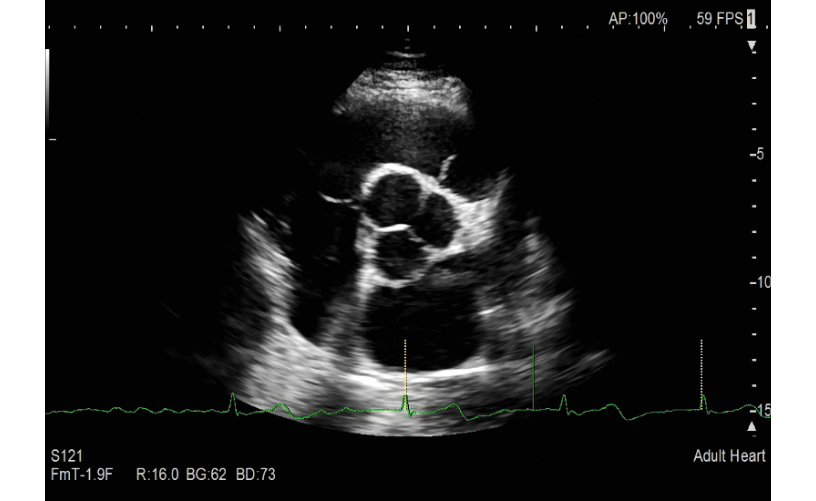

A wide range of essential image adjustment parameters dedicated to high cardiac image quality; a variety of technologies to reduce confounding factors that inhibit signal fidelity such as patient dependent variability; transducers, image processing algorithms, monitor display: PURE SYMPHONIC ARCHITECTURE providing premium level image clarity for cardiac diagnosis.

The phased array transducer has been designed to realize the high spatial, temporal and contrast resolution especially required for cardiology. With an improved shape that is comfortable to hold and fits easily in intercostal spaces, it can reduce variable factors such as user skill- and patient disease-dependencies that can inhibit image clarity.

The transmission/reception technology for LISENDO 880LE realizes significant S/N improvement and reduces focal dependency whilst providing excellent penetration at higher frequencies. eFocusing offers a real-time display not modified by image processing, selected by a one-touch operation.

The Fujifilm Group's image processing technologies evolved from former models are further refined for LISENDO 880LE. Combined with the newly developed transducers and eFocusing technology, they deliver imaging with outstanding definition which can be adjusted for each user's preference.